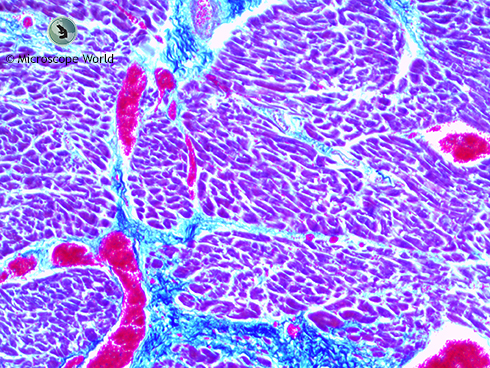

Human Cardiac Muscle under Microscope

Human cardiac muscle captured under the RB30 microscope at 40x magnification with a 5mp microscope camera.